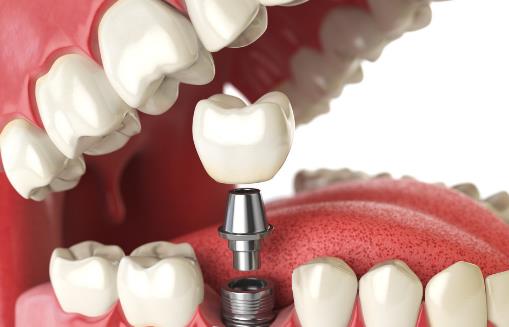

人工種植牙同傳統假牙相比、具有許多突出的優點:

1、它的咀嚼功能大大優于其它假牙;

2.具有很強固位和穩定性,可象真牙一樣扎在患者的口腔里;

3.可少磨或不磨自己的真牙;

4.不需要活動牙必備的基托和卡環,沒有大面積的基托導致的味覺遲鈍與不舒適感;

5.體積小不外露金屬、美觀,更有利于保持口腔清潔衛生。

6.對于某些用傳統假牙修復困難或效果不佳的患者,口腔種植牙更具優越性。